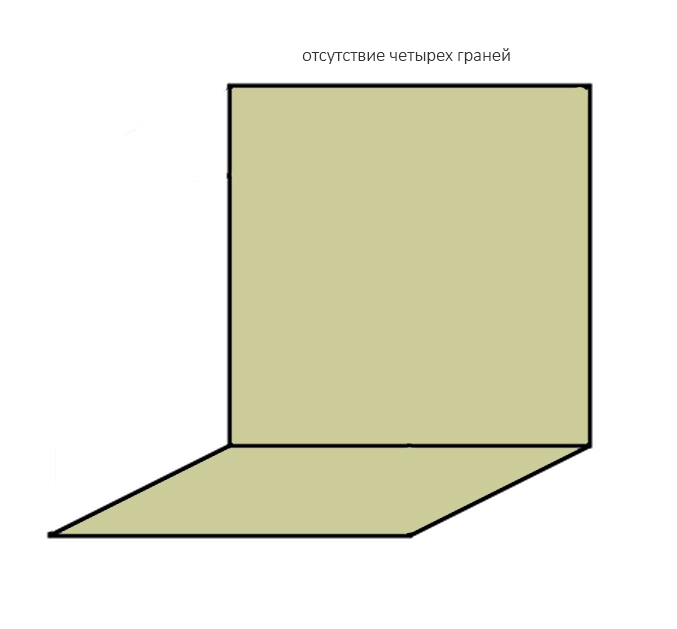

Любые костные дефекты челюстей мы можем представить в виде шестигранника (гексаэдра) или, если хотите, в виде куба:

По отсутствию одной или нескольких граней мы можем легко их классифицировать.

И крайняя степень — отсутствие четырёх или пяти стенок:

ставит под сомнение целесообразность проведения остеопластики, поскольку добиться качественного результата в таких случаях крайне сложно:

но вполне возможно: